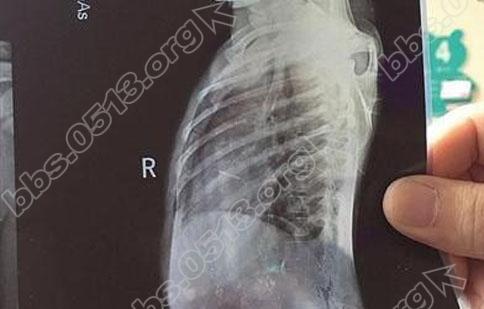

据媒体报道,4岁女童心脏跟肺部附近插着一根3厘米的绣花针,正是这个绣花针导致女童发热。那么为何女童胸口会有3厘米的绣花针存在呢?一起去看看吧。/ p; d3 j" K! S+ q# a. q

0 U3 D5 a: L2 Q9 h. j7 I 10月8日,玲玲因感冒咳嗽发烧到医院就诊,经过一段时间治疗,玲玲的感冒有好转,但咳嗽却一直不见好。医生通过照片发现,孩子的胸壁处,竟然有一个金属样的异物。检查发现,玲玲的胸壁确诊有针样异物,就在心脏和肺部附近。专家表示如果在体内生锈,会引起感染或发生破伤风,更危险的是,因为靠近心脏和肺部,针在身体内很可能通过肌肉运动进入心脏或肺部。不管是进入心脏还是肺部,后果都不堪设想。

26日,医生们为玲玲实施了手术,通过她的左侧胸壁一个1厘米左右的切口,取出了3厘米的绣花针。代医生说,绣花针取出时已在玲玲体内生锈,孩子出现发热的情况,可能就是因这枚绣花针引起的。